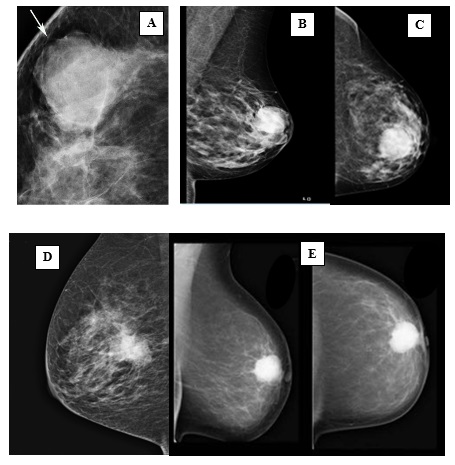

Características mamográficas del CMTN

Los resultados de las características mamográficas en nuestra población con CMTN (n = 17) se describen de la siguiente manera: la mayoría presentó un tejido fibroglandular ACR B (n = 10), lo que equivale al 60% de la muestra total. Le siguió un ACR A (n = 3). En cuanto a la descripción de los nódulos, se reportaron como ovalados en el 70% de los casos, con márgenes circunscritos en el 47%. Además, se observó que eran hiperdensos en el 76% de los casos y no presentaban calcificaciones asociadas (100%). No se encontró evidencia de adenopatías axilares ni lesiones asociadas mediante este método diagnóstico.

Los hallazgos radiológicos, tanto en mamografía como en ecografía, describen características comunes de los nódulos en pacientes con CMTN, incluyendo la forma ovalada, los márgenes circunscritos o lobulados, la hipoecogenicidad y la ausencia de hallazgos acústicos posteriores. Estos resultados subrayan la importancia de la evaluación exhaustiva de las características mamográficas y ecográficas en el diagnóstico y la estratificación de los CMTN, que presentan concordancia con lo descrito en la bibliografía médica actual revisada.

Anexo 1. Imágenes mamográficas de CMTN